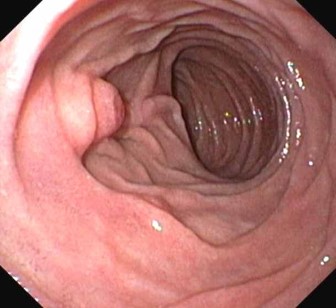

- Darmspiegelung / Sigmo – Kolo – Ileoskopie

Diagnostische Koloskopie zur Abklärung abdomineller Beschwerden, ggf. mit Probeentnahmen (z.B. bei Verdacht auf chronisch-entzündl. Darmerkrankung)

Zur Abklärung von Oberbauchbeschwerden, Schluckbeschwerden, Sodbrennen etc.